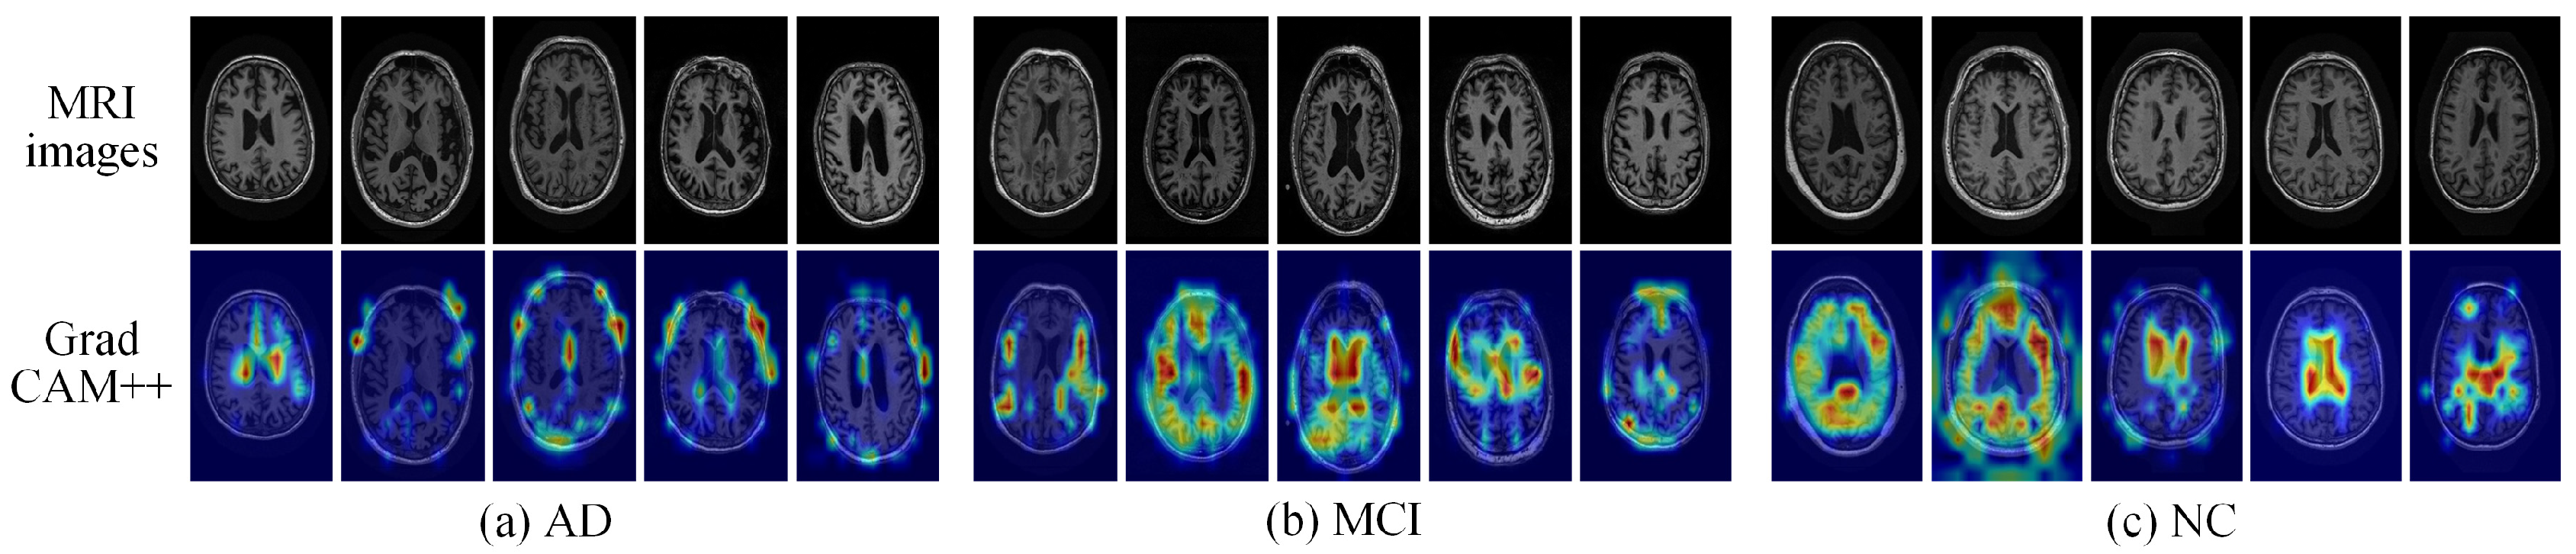

(1) Grad-CAM++ feature visualization. In the clinical diagnosis of AD, MRI typically focuses on pathological features such as the hippocampus, entorhinal cortex, and temporal lobe, as well as ventricular enlargement. Previous studies have identified these regions as key biomarkers, including hippocampal and cerebral atrophy, cortical changes induced by amyloid plaques, and pathological features in the amygdala, entorhinal cortex, and hippocampal formation [47,48,49,50,51,52]. Based on this medical consensus, this study randomly selected AD, MCI, and NC samples from the test set for Grad-CAM++ visualization analysis. As shown in Figure 5, the activation regions of AD and MCI in the Vi-ADiM model overlap closely with the aforementioned clinical-pathological regions. The model exhibits significant weight distribution, particularly in regions associated with memory functions such as the hippocampus and temporal lobe. This consistency demonstrates that Vi-ADiM can accurately capture clinically relevant features. In terms of category discriminability, the AD heatmap shows significant differences from the NC heatmap, while the MCI activation regions lie between the two, consistent with the medical definition of MCI as a precursor stage to AD. Additionally, the heatmap distribution in the NC group is relatively scattered, suggesting that the model tends to classify the normal category based on overall brain morphology rather than local lesions. Through local perturbation interpretation and structural correlation validation, the feasibility and reliability of Vi-ADiM in assisting diagnostic decision-making have been demonstrated.